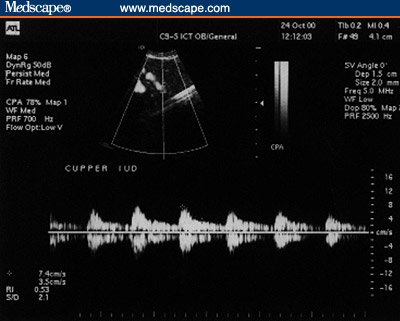

Figure 3. Copper IUD. (3A, Sagittal view [Note the

echogenicity of the device throughout its length)]; 3B, Transverse

view.)

Figure 4. Copper IUD. Subendometrial flow. (4A, 1 month post

insertion; 4B, 1 year post-insertion [Note the rich flow even a year

post insertion of the IUD.])